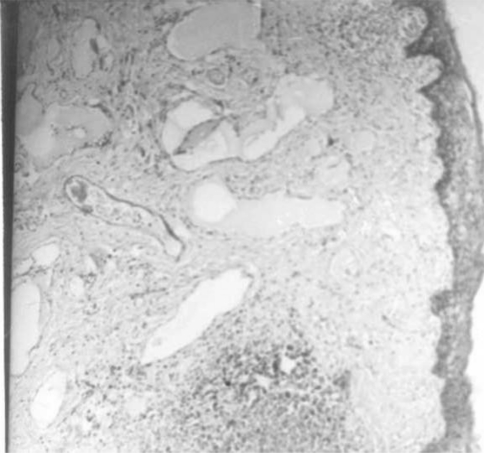

On microscopic examination, the mass was seen to be lined by hyperplastic stratified squamous epithelium (Fig. 3). Stroma was lose and edematous with multiple haphazardly arranged dilated lymphatic channels (Fig. 4) with lymphoid follicles in the intervening areas (Fig. 5).

Fig. 3.

Hyperplastic stratified squamous epithelial lining (H and E staining, ×250)